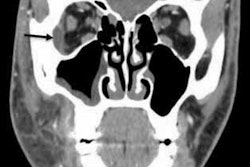

(A) Panoramic radiograph reveals needle fragment located at the anterior ramus of the left mandible. (B) A CBCT image of the lost needle, with two injection needles used as reference points.In this case, the man's dentist referred him to the maxillofacial and oral surgery department to have a suture needle removed from his left buccal mucosa. The needle was supposed to be tied with nylon, but the dentist cut it while performing explantation and local flap surgeries due to the man's chronic peri-implantitis, they wrote.

During an oral exam, a surgeon inserted two needles perpendicularly into the man's left buccal mucosa as reference points to better locate the lost suture needle. Then, the patient underwent a CBCT scan that revealed the broken needle was located above the injection needle and below the maxillary tuberosity, the authors wrote.